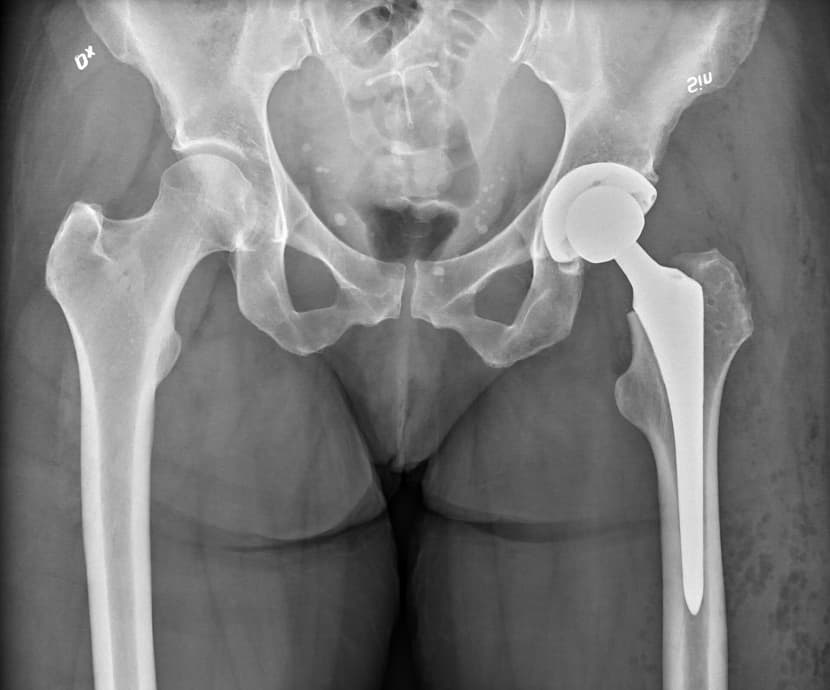

Ilustracija

- Iako sam kao traumatolog obavio mnogo takvih operacija, moram reći da su kod zahvata na kuku kirurzi ortopedi puno bolje rješenje. To je posebno važno prilikom obrade zdjelične kosti koja je na nekim dijelovima prilično tanka i krhka a iza nje se nalaze osjetljivi organi i, što je najopasnije, ilijačna arterija. Ako se ona probije situacija vrlo brzo postaje kritična i potrebna je hitna intervencija. Kada se to dogodi u nedjelju navečer onda je problem još veći, smatra naš sugovornik.